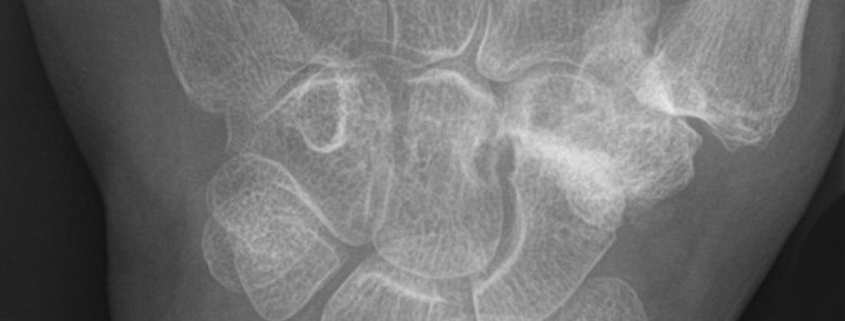

Wrist arthritis is usually diagnosed through a combination of medical history, physical examination, and imaging tests. Your doctor may also require lab tests to determine if the arthritis is due to an autoimmune disorder.